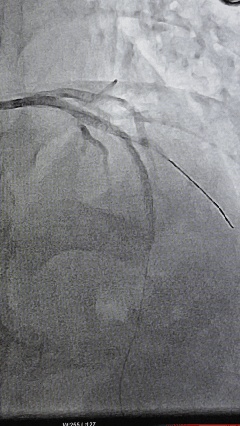

进入介入科后,冠脉造影结果显示,患者的前降支已从近段完全堵死,情况十分紧急。心内科团队迅速展开手术,穿刺、造影、球囊扩张、支架植入……每一个步骤都精准而迅速。对于心率过慢、血压过低的患者,手术风险极高,操作需如履薄冰。团队不仅要争分夺秒地开通被血栓堵塞的冠状动脉,恢复心肌供血,还要时刻维持患者生命体征的稳定,应对术中可能出现的任何突发状况。随着血流恢复,患者的心率、血压逐步回升,成功为患者开通了闭塞的“生命线”。

IMG_257 术前